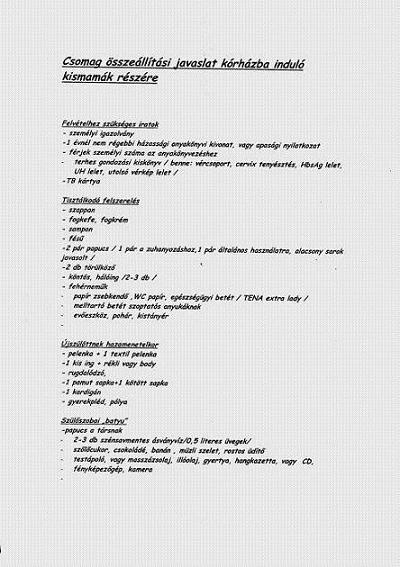

Nyugdtan kerdezz a korhazzal kapcsolatban akar 1000et is,nagyon szivesen valaszolok!!!!!!!!!!!!!!!!!!!!!!!!!!!!!!!!!!!

Bentmaradas: en hetfon szultem,csutortokon mar jottunk haza

Szoval altalaban 3 nap.

DE akinek mar nem az elso babaja,azok kozul nagyon sokan 2 nap utan mentek.De altalaban a kismamik szoktak kerni,hoygmehessenek,es ha engedik,mert minden ok,babaval-mamaval,akkor mehetnek.Csak eslo babasoknal megvarjak a tejcibelovellest,meg megmutizzak a szopizast,stb..

De egy nem elsozor szulonek ezek mar nem ujdonsagok.

Szobak:2 agyasbol van a legtobb,1 db 4 agyas van.Es vannak fizetos 1 agyasok.

A 2agyasnal (en abban voltam) ugy van,hoyg 2db 2agyas szobahoz van egy kozos zuhi-wc,ami a ket szoba kozott van es a folyosorol tudsz bemenni.A 4 agyasnal van a szobaban zuhi-wc.Az egy agyasnal meg persze van bent.

Latogatas:nem mehet be senki a szobaba,de ez sztem nem is baj.A gyerekagyas resz tok zart,ott kimesz a folyoso vegere,ahol egy uvegajto van,es oda kitolod magaddal a babot,az ajtonal pedig mindenki megcsodalhatja.

Aztan Te kimehetsz dumizni a rokonokhoz,a baba meg az ajto tuloldalan marad